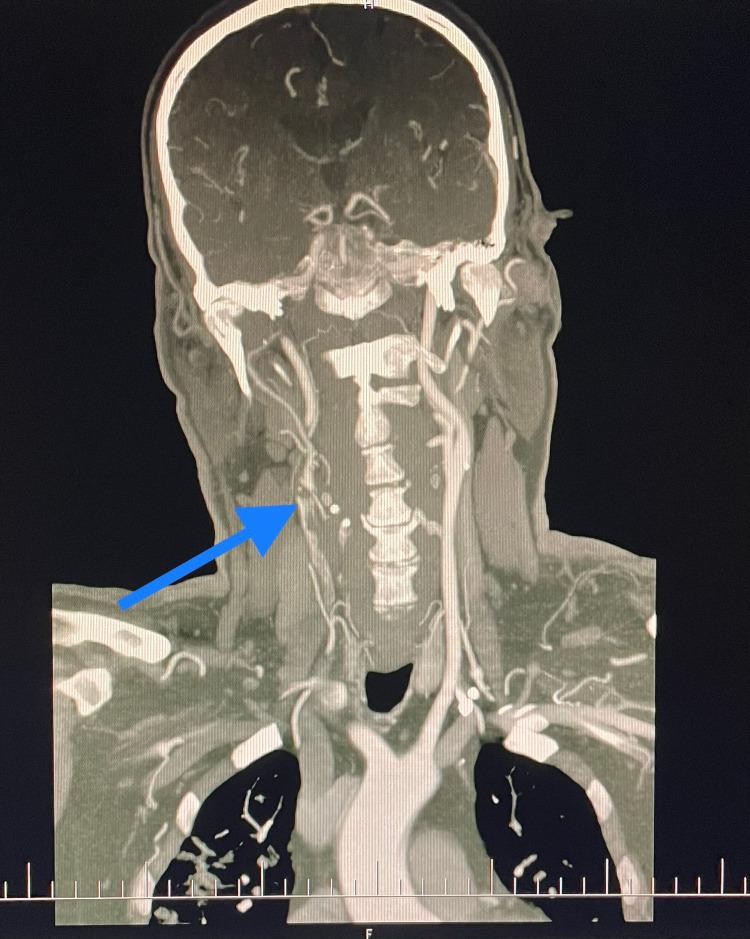

Coronavirus disease 2019 (COVID-19), caused by severe acute respiratory syndrome-coronavirus 2 (SARS-CoV-2), was initially discovered in December 2019 in China and rapidly spread all over the world to become a pandemic. The most common symptoms of a disease are fever, cough, generalized body ache, weakness, dyspnoea, nausea, vomiting, and diarrhea. Among vascular complications of COVID-19, the venous thrombotic complications, like pulmonary embolism and lower limb deep veins thrombosis, are not uncommon. But data about arterial thrombotic complications of COVID-19, especially carotid thrombosis, are still limited. We are describing a case of stroke due to thrombosis of the right carotid arteries, in a patient who had recovered from asymptomatic COVID-19. A 66-year-old male with arterial hypertension presented to the emergency department with a history of repeated collapse, dysarthria, weakness in the left extremities, and a drop in the left angle of his mouth (National Institutes of Health Stroke Scale [NIHSS]-4). The patient was swabbed for COVID-19 which was negative. A computed tomography angiography (CTA) was obtained which showed thrombosis in the branching point of the brachiocephalic trunk (BCT) continuing into the right subclavian artery (SA) and also into the right common carotid artery (CCA), with a subtotal occlusion of the right CCA, extending into the internal carotid artery (ICA) as well. From the apical lung tissue caught during the CT scan, bilateral, irregular widespread ground-glass opacifications, as well as consolidations and small reticular changes were seen in the lungs, which is typical for COVID-19 infection. A quantitative antibody test for COVID-19 infection was performed with the results showing a strong positivity for IgG antibodies, indicating previous COVID-19 infection. The patient was indicated for a standard carotid thrombectomy, which was performed without complications. It seems that one of the important factors that led to the formation of the thrombus in the carotid arteries was COVID-19 infection-induced inflammation in the atherosclerotic carotid vessels and generalized hypercoagulability as well as hyperviscosity. COVID-19 infection is an independent and important risk factor for the formation of an arterial thrombus during the acute illness and in the early post-COVID-19 period also, regardless of the severity of its course. Prophylactic anticoagulation is needed not only at the time of acute illness but also at the early post-COVID-19 time.

2019冠状病毒病(COVID-19)由严重急性呼吸综合征冠状病毒2(SARS-CoV-2)引起,于2019年12月在中国首次发现,并迅速蔓延至全球,成为大流行病。该疾病最常见的症状是发热、咳嗽、全身酸痛、乏力、呼吸困难、恶心、呕吐和腹泻。在COVID-19的血管并发症中,静脉血栓形成并发症,如肺栓塞和下肢深静脉血栓形成并不少见。但关于COVID-19动脉血栓形成并发症的数据,尤其是颈动脉血栓形成的数据仍然有限。我们正在描述一例在无症状COVID-19康复后的患者中,因右颈动脉血栓形成导致中风的病例。一名患有动脉高血压的66岁男性因反复晕厥、构音障碍、左肢无力和左侧口角下垂(美国国立卫生研究院卒中量表[NIHSS]-4)的病史就诊于急诊科。对该患者进行了COVID-19拭子检测,结果为阴性。进行了计算机断层扫描血管造影(CTA),显示头臂干(BCT)分支点处血栓形成,延续至右锁骨下动脉(SA),并延伸至右颈总动脉(CCA),右CCA几乎完全闭塞,也延伸至颈内动脉(ICA)。在CT扫描过程中获取的肺尖组织中,肺部可见双侧不规则广泛的磨玻璃样混浊,以及实变和小网状改变,这是COVID-19感染的典型表现。进行了COVID-19感染的定量抗体检测,结果显示IgG抗体呈强阳性,表明既往感染过COVID-19。该患者接受了标准的颈动脉血栓切除术,手术无并发症。似乎导致颈动脉血栓形成的重要因素之一是COVID-19感染引起的动脉粥样硬化颈动脉血管炎症、全身高凝状态以及高黏滞血症。无论COVID-19病程的严重程度如何,COVID-19感染都是急性疾病期间以及COVID-19后早期动脉血栓形成的独立且重要的危险因素。不仅在急性疾病期间,而且在COVID-19后早期都需要预防性抗凝。